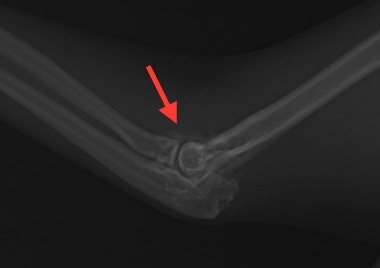

このレントゲン写真は右前脚の痛みがあるという主訴で来院した4歳の猫のものです。上が右前脚、下が左前脚です。拡大するとよくわかるのですが、右の肘関節の周囲がモヤモヤと白く見えているのがわかります(赤矢印)。左肘にはこのような変化は認められません。関節炎が慢性化すると、骨や軟骨の変性が生じ、骨化してレントゲンでも変化が確認できるようになります。レントゲン上は些細な変化ですが、肘関節には大きな異常が生じており、慢性的に痛みを感じるようになります。この子の場合は非ステロイド系鎮痛剤の注射で症状が改善したため、経過観察となっています。